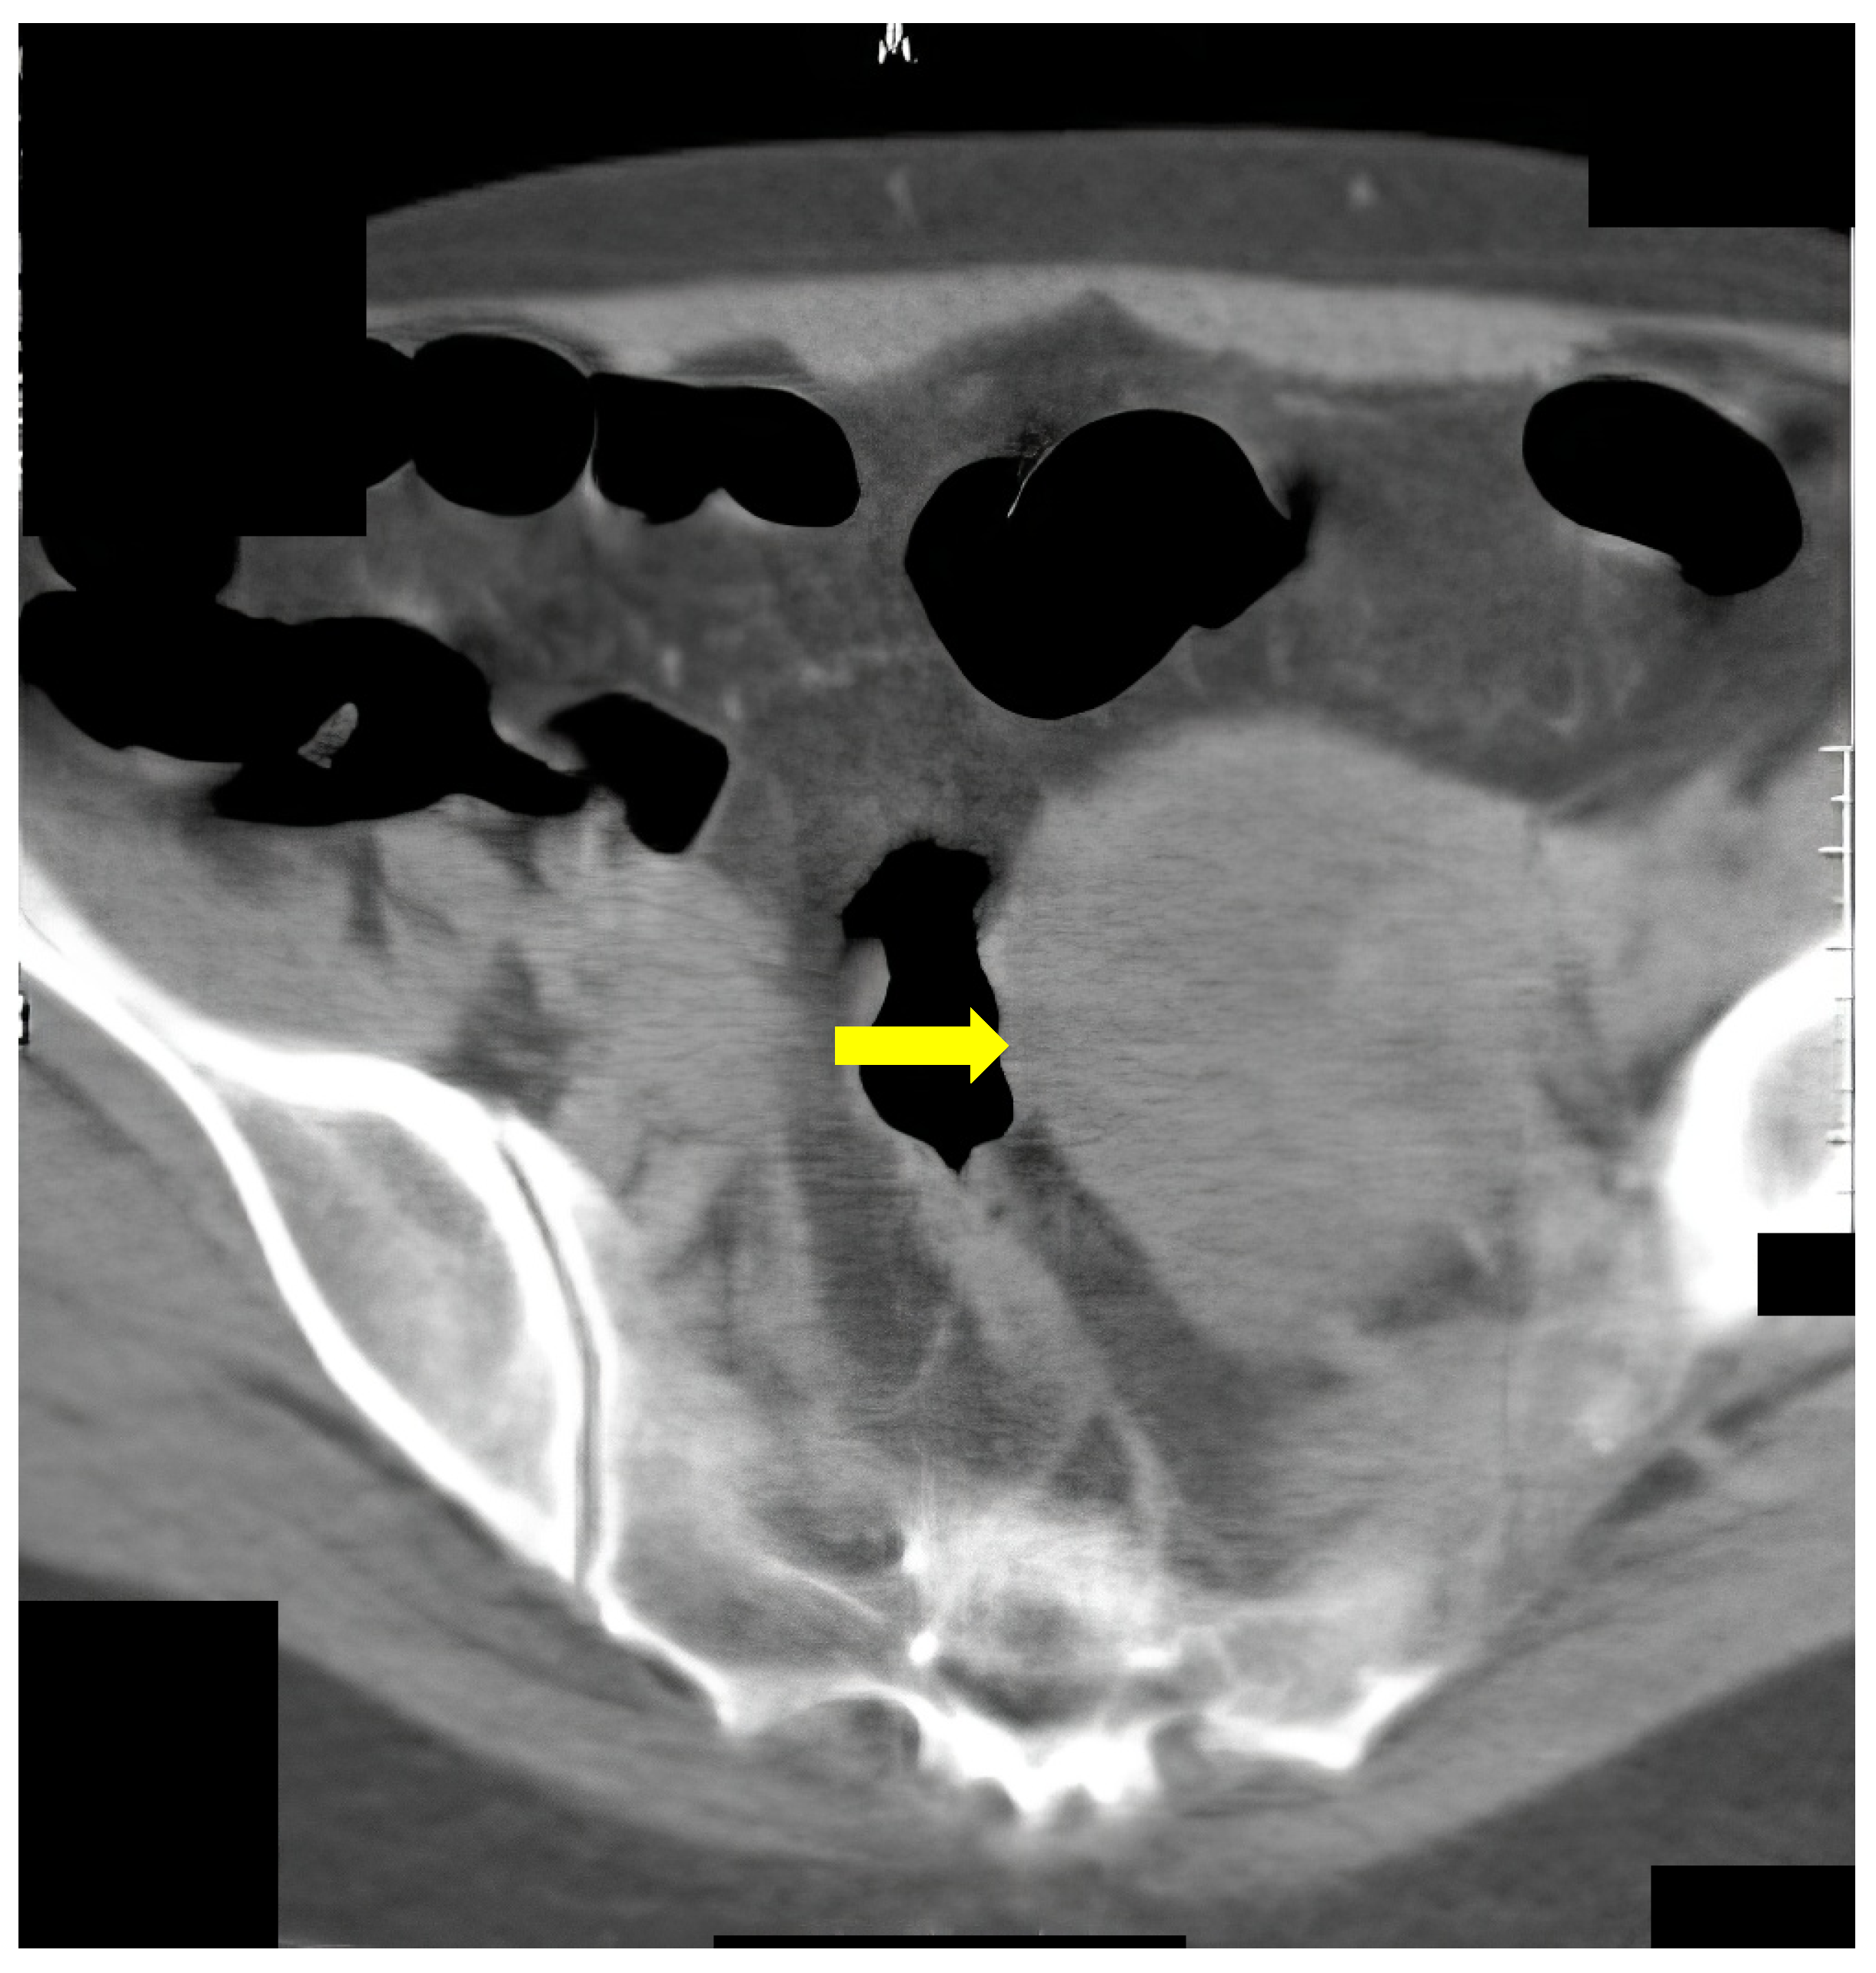

The following case was an 80-year-old patient who underwent FCS, on which there was evidence of compression of the colon. CT colonography showed tumor formation with irregular outlines and inhomogeneous density arising from the caecum (Figure 6).

Figure 6.

CT colonography-axial slice; 80-year-old patient with incomplete FCS obturation from extraluminal origin was suspected (yellow arrow). After CT colonography, cancer of the cecal valve was found.